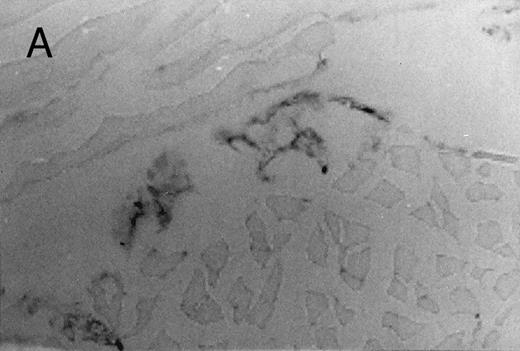

Basophilic cell migration induced by human recombinant RANTES 10 ng (C) and MCP-1 10 ng (D) into sites of injection. The sections were stained with Toluidine blue (0.1%) and analyzed at a magnification of ×40 (Nikon Diaphore). (A) represents a control and (B) is a positive control where FMLP was used at 10−6 mol/L. This representative experiment was found to be reproducible and has been performed at least three times.

Chemotactic effect of human recombinant RANTES and MCP-1 on basophilic cells.Recently it has been reported that RANTES and MCP-1, -2, and -3 are chemotactic agents for human T lymphocytes.23 26 In this study we evaluated the selective chemotactic effects of RANTES and MCP-1 on basophilic cells. Figure 3 shows an increased number of basophilic cells after a 50 μL intradermal injection of FMLP (10−6 mol/L), RANTES 10 ng and MCP-1 10 ng, while PBS (vehicle) did not produce any appreciable effect. The infiltrated basophilic cells were colored with Toluidine blue (0.1%) and counted in the optic field using a grating of size 5 × 5 mm, under an optic microscope (× 40). In Table 2 results indicate that RANTES at 20 and 10 ng is more potent than equal doses of MCP-1 (<0.05 and 0.01, respectively). The highest number of basophilic cell accumulation in the skin injection sites was obtained with LPS (10 ng/50 μL) (193 ± 21), while FMLP (10−6 mol/L) (127 ± 14) was found to be less effective.